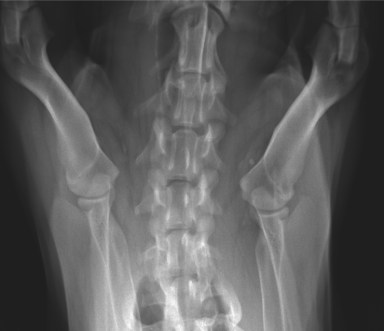

Signalement: Labrador de 2 ans, femelle stérilisée.

Histoire clinique: Dysphagie, douleur au cou, boiterie de non appui MTG, parésie MPs pire a gauche. Lésion suspectée au niveau cervical caudal latéralisée à gauche.

La lésion semble localisée au niveau de l’atlas. Serait-ce une fracture de cette vertèbre cervicale qui entraîne une dysphasie par compression de l’oesophage et douleur au courant? Si fracture il y a, quelle en serait la cause ? Est-ce que la compression de la moelle épinière à ce niveau pourrait être responsable de la paresie des MPs et de la boiterie de non appui au MTG?

Salut Robert ! La forme de l’atlas est due à sa rotation axiale, entraînant les ailes dorsalement et ventralement. C’est pour ça aussi que le processus odontoïde est si évident. On peut donc dire que ce processus est intact. Continue ton exploration des images… 😉